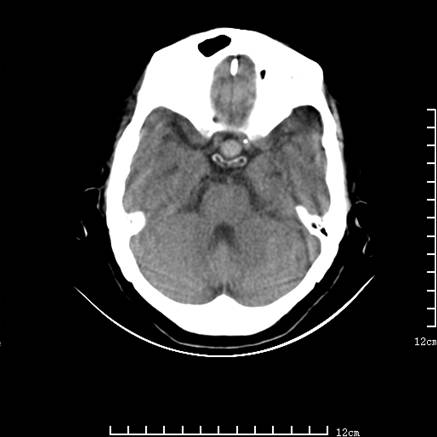

标题: V0514:女,72岁,偶有头晕,自诉记忆力减退,来诊。 [打印本页]

标题: V0514:女,72岁,偶有头晕,自诉记忆力减退,来诊。

是拉特可囊肿(rathke cyst)吗?

考虑垂体瘤可能性大

1、考虑垂体腺瘤。

2、脑萎缩ct表现。

垂体腺瘤可能性大!另:轻度脑萎缩!

考虑垂体腺瘤可能性大。脑萎缩。

考虑垂体腺瘤可能性大。脑萎缩。  建议mri 检查

垂体瘤,建议mri

垂体腺瘤